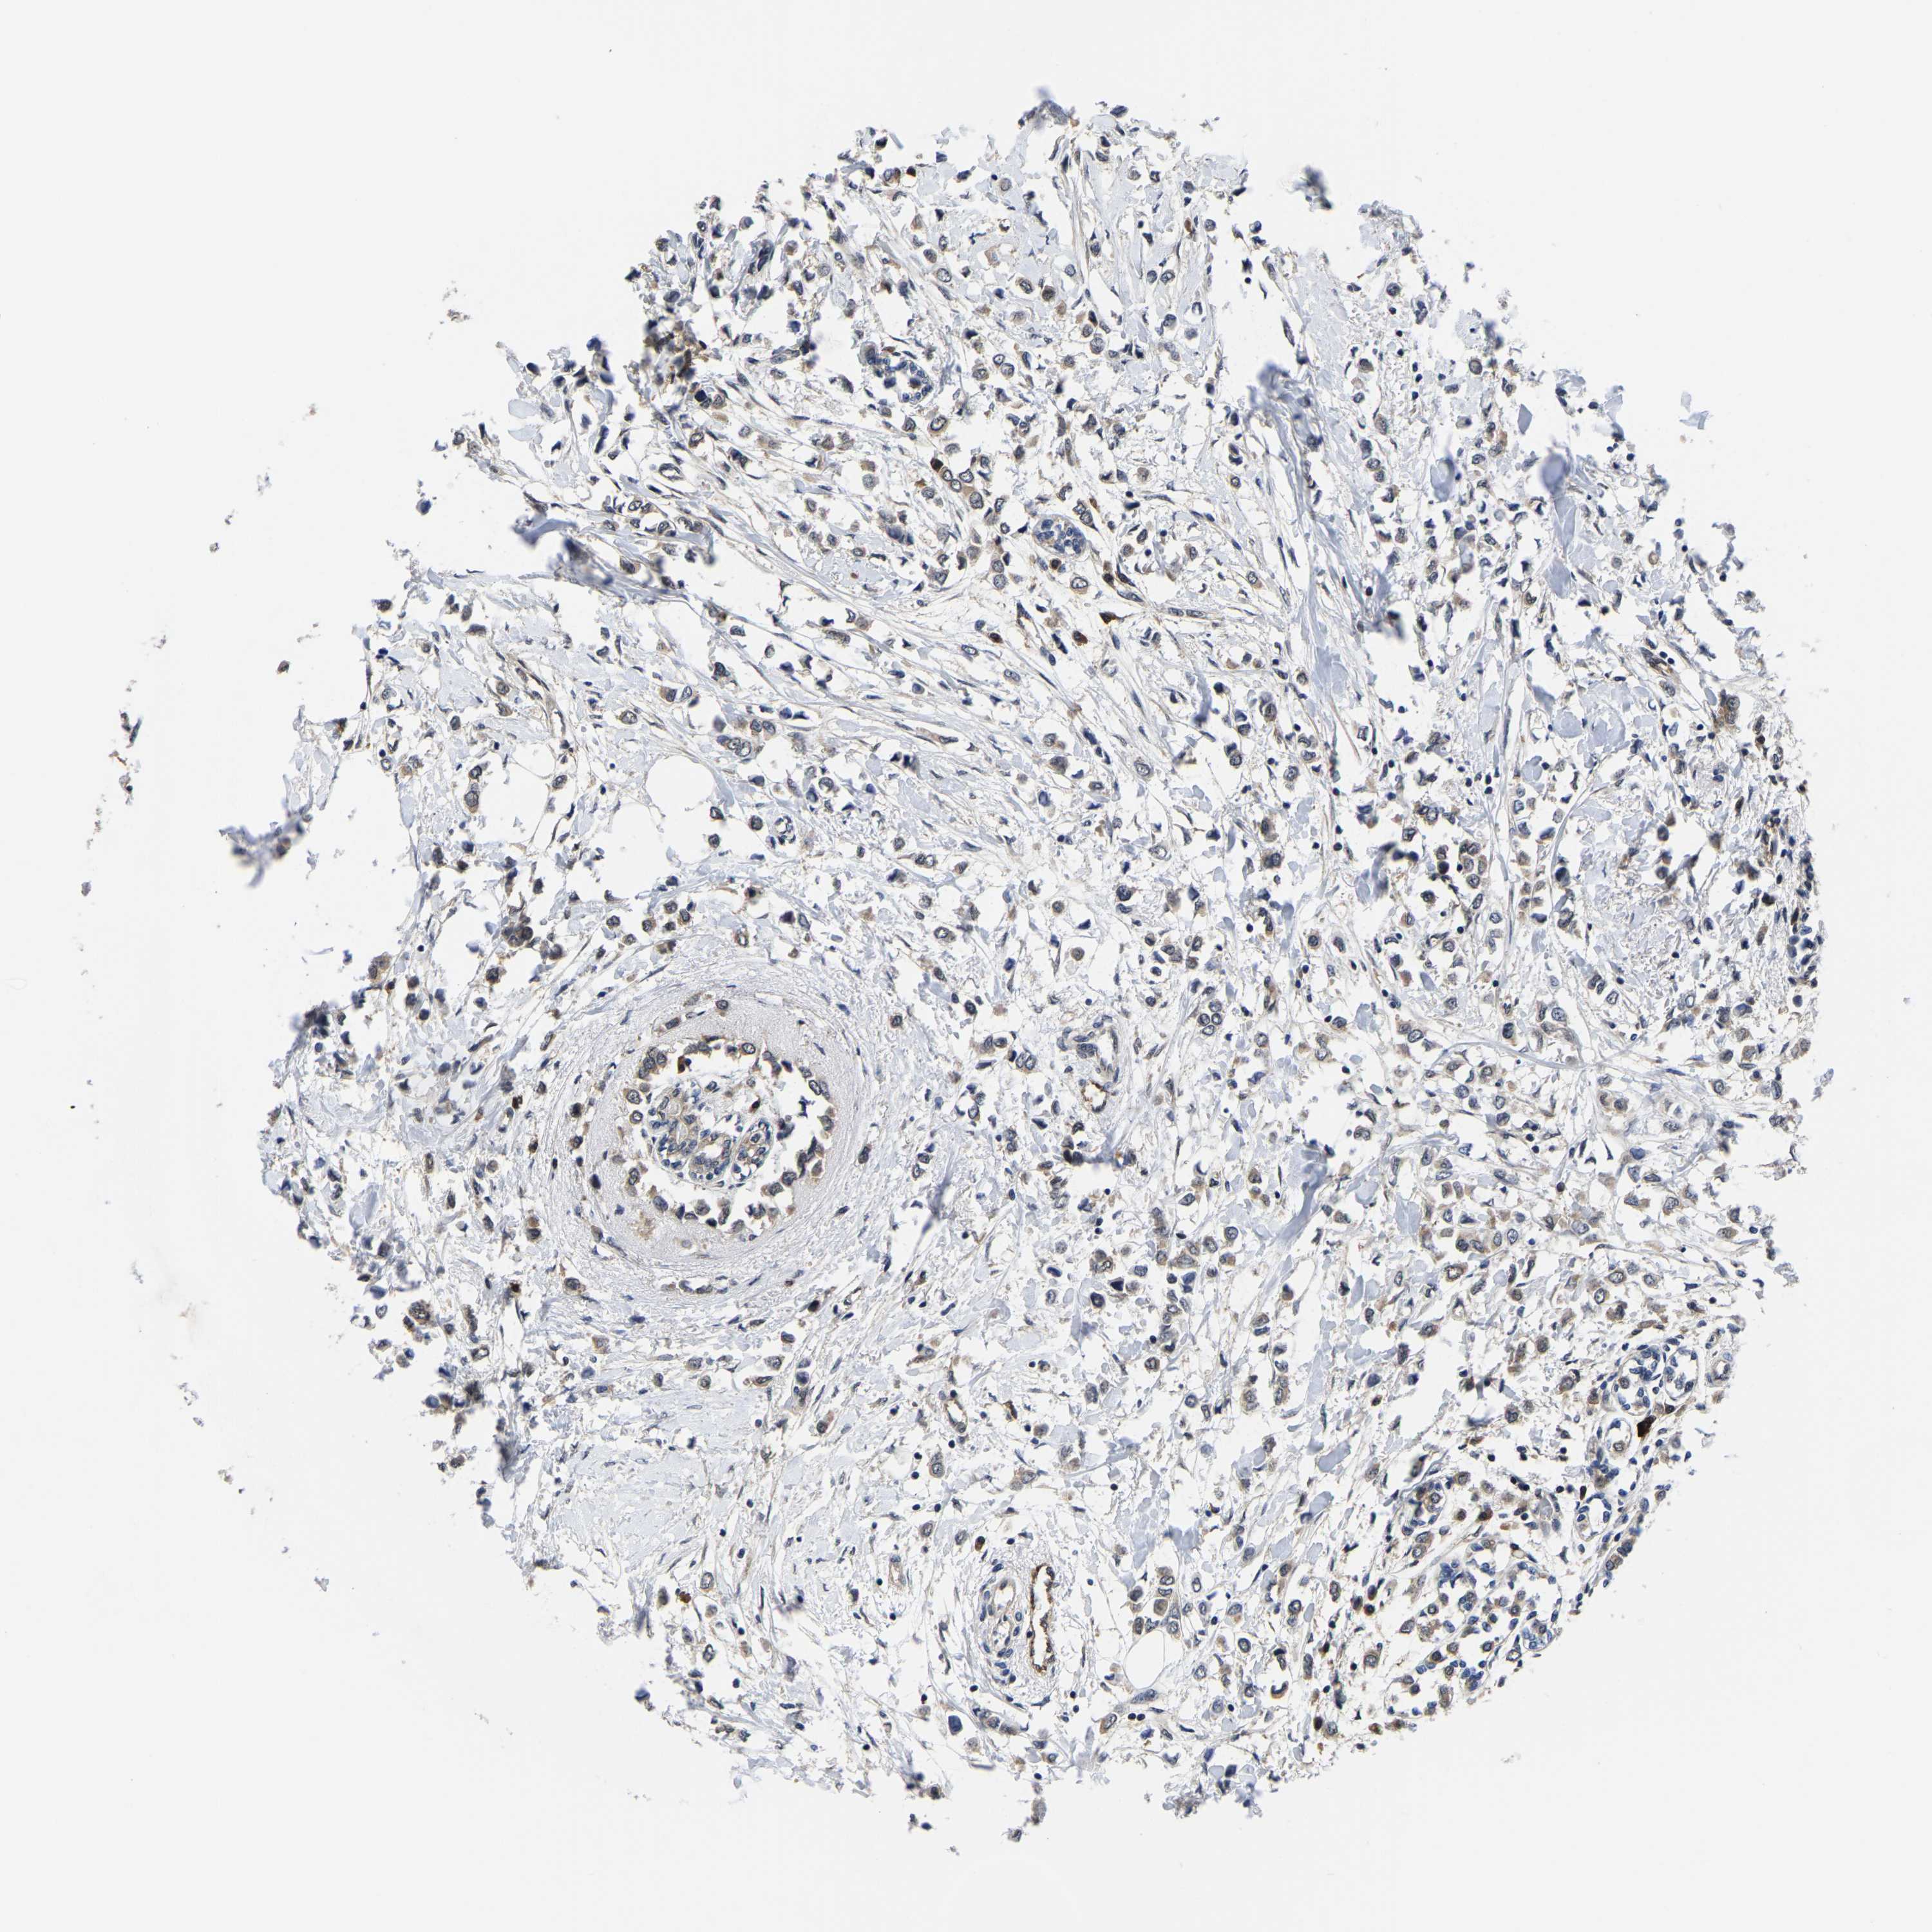

BRCA TCGA BRCA VALIDATION PROTEIN EXPRESSION

ANTIBODIES

AND

VALIDATION